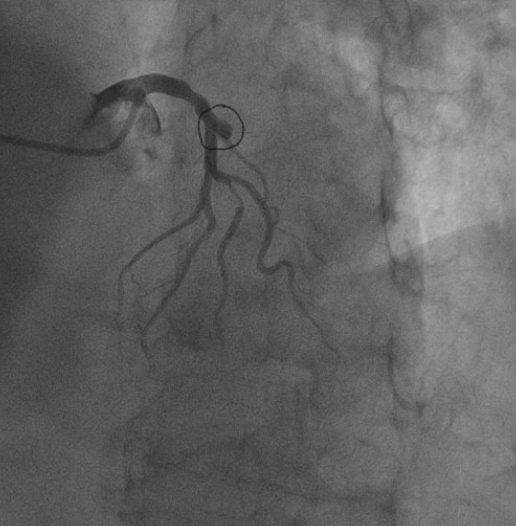

急性心肌梗死发病急、病情凶险、死亡率高,是导致中老年人猝死的主要原因之一,当高龄老人遭遇急性心梗时,凶险更是不言而喻。近日,我院心血管内科成功救治一名90岁高龄的心肌梗死患者,术后患者康复出院并送来锦旗。这是我院心肌梗死患者中年龄最大、成功完成急诊PCI手术的女性患者。

80岁以上的患者,因身体的各种功能明显衰退,行心脏支架植入术风险很大,几乎是手术的雷区。但如果不进行介入精准治疗,延误了最佳的治疗时机,心肌坏死情况可能会加重,随时有生命危险。心肌梗死猝死率较高,越早治疗,效果越好。